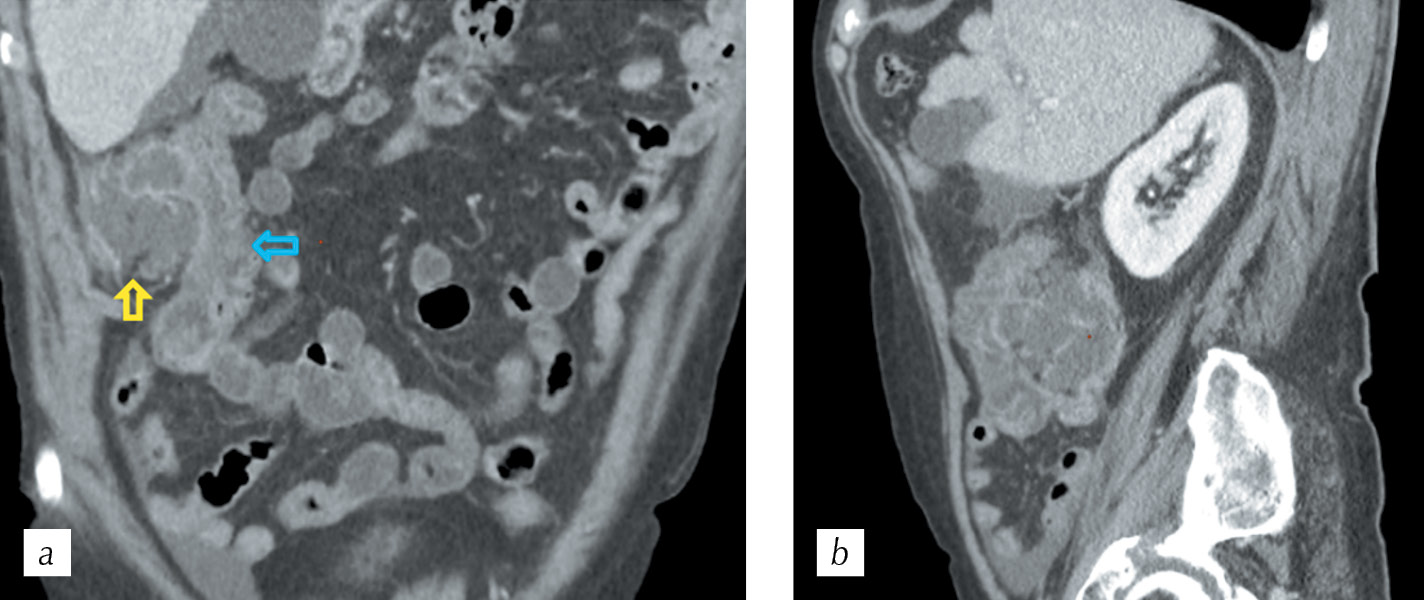

For a comparative assessment, the results of the examination of the patient who was admitted to the hospital with non-specific symptoms were presented. According to the ultrasound results, the mass lesion in the abdominal cavity palpable during physical examination was presumably associated with the ascending part of the colon. While performing the PCT, a paracolic abscess was detected in the right lateral canal which was associated with the lumen of the ascending colon. The walls of the intestine at the level of the mass lesion were circularly thickened (Fig. 9). On the perfusion cards, a predominantly low BF was detected in the thickened walls of the intestine, with an observation of single hypervascular inclusions (Fig. 10). While measuring blood flow parameters in the area of maximum perfusion (ROI 2) and the contralateral wall of the intestine (ROI 3), the range of numerical values of BF was 9–67 ml/100 g per min (Figure 11a), and the curves on the density – time plot showed similar trends in density at the points of interest, without the formation of peaks typically noted for tumors (Fig. 11, b). The abscess was drained, and the effects of colitis regressed following conservative therapy.

Fig. 9. HCT. Multiplanar reconstructions in: a — coronal and b — sagittal planes in the portal phase demonstrating thickened walls of the ascending colon (blue arrow) and paracolic abscess in the lateral canal (yellow arrow)

Рис. 9. Спиральная компьютерная томография. Мультипланарные реконструкции в: a — корональной и b — сагиттальной плоскостях в портальную фазу сканирования — стенки восходящего отдела ободочной кишки (голубая стрелка) утолщены, параколический абсцесс в латеральном канале (желтая стрелка)